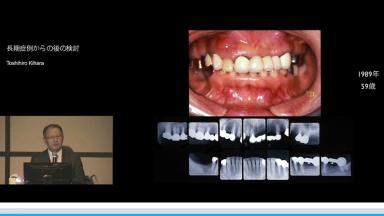

長期症例からの後の検討

Toshihiro Kihara

インプラントの成功率は95%以上であるのに対し、日本では補綴歯の75%が無髄歯であるため、長期的にみると天然歯がなくなりインプラントが残る。その背景には、不適切な根管治療、補綴物による歯根破折が多いことがある。

欠損部隣在歯のトラブルフリー曲線でインプラントと天然歯、失活歯と生活歯を比較し、実際の症例を提示しながら最小限の治療で最大限の効果を得る方法が解説された。

インプラントが残るからこそ、最終設計が重要であり、患者の年齢や成功する要素を考慮して、1回目の治療時にもう一度大きく治療する必要のないようにするべきであり、その際に正常像の範囲内に入るよう治療を行うべきであると結論づけられていた。